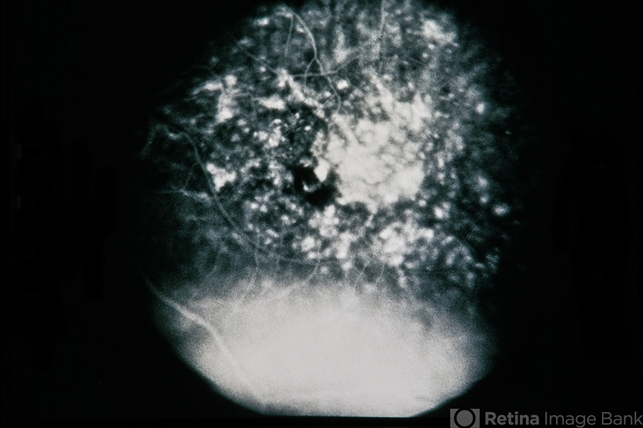

- cystoid macular edema (CME), silicone oil

- 66-year-old male, CME s/p silicone oil.